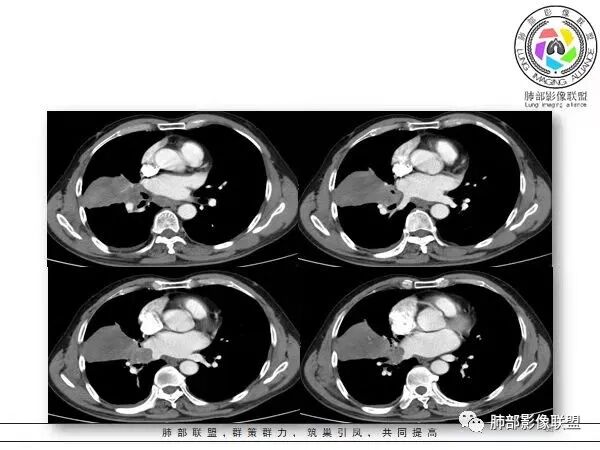

慢性咳嗽,抗炎复查无好转,原右肺中叶实边,外侧段支气管开口阻断,复查无好转,逐渐向下叶外前基底段融合形成大肿块,边缘膨隆,密度不均匀,坏死轮廓不清,内血管束破坏,累及中轴间质厚,外围分布,方向恶性,与炎性肉芽肿鉴别,隐球荚膜抗原先排查!

女,74岁,咳嗽咳痰加重一周入院,右肺中叶大片实变影,边界清晰,病灶内密度不均匀,右肺中叶支气管变窄,增强扫描病灶明显强化,考虑恶性病变能,鉴别肺脓肿。

右肺中叶实变,支气管开口阻断,边缘膨隆,密度不均匀,坏死边界清晰,胸膜累及,。一般抗感染治疗无效。考虑恶性。

老年女性患者,慢性病程,两次活检均提示炎性病变,胸部CT:右肺中叶大片实变密度影,边界尚清楚,部分收缩,部分膨隆,内部有低密度坏死,坏死边界清楚,无明显结节感,无分割,总体考虑炎性病变,机化性肺炎,NTM,慢性肺脓肿,鉴别:恶性,腺癌

右肺中叶大片实变,内见大片的坏死,中叶外侧段支气管阻塞,相邻胸膜增厚,间隔约四个月后复查,发现低密度坏死内可见气泡影,老年人,反复迁延不愈的病变要考虑恶性,首先考虑腺癌伴感染。鉴别慢性脓肿。

右肺胸膜下实变,跨叶,形态不规则,局部边缘膨隆,中叶支气管外侧段进入后阻塞伴不张,不均匀强化,其内坏死边界欠清晰,复查无吸收,考虑腺癌,鉴别慢性炎症伴脓肿

右肺大片状高密度灶,跨叶,密度不均,边缘膨隆,支气管阻塞,粘液栓,不均匀强化,其内坏死边界欠清晰,复查无吸收,考虑腺癌,鉴别慢性炎症,脓肿

胸部CT:右肺中下叶大片实变影,界清,边缘膨隆为主,中叶外侧段支气管截断。增强不均匀强化,边缘可见血管影迂曲模糊,内见条带状低密度影。治疗后病变进展。考虑恶性,鳞Ca?鉴别TB、OP。

老年女性,慢性病史,炎性指标稍高,肿标正常,右中下肺大片实变,跨叶生长,边界清,收缩力差,膨隆生长为主,支气管杵状截断,均匀强化,其内坏死边界清,可见悬浮气泡,整体观察,病灶膨隆生长为主,邻近肺野无播散灶,形态单一,尽管慢性病史,影像不支持OP和TB,支气管截断呈杵状,肿标正常,均匀强化,虽是高龄患者,诊断恶性肿瘤有点牵强,综和分析,首选炎性病变放线菌感染,其次考虑低度恶性占位炎机母。